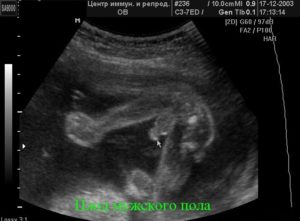

Современные технологии позволяют с почти 100%-ной вероятностью определить пол ребенка, начиная с 16 недели его развития. Узнать, кто же появится, будущим родителям и родственникам хочется как можно раньше. Поэтому многие используют приметы для новорожденных. Как определить вероятность рождения мальчика, девочки?

УЗИ является самым достоверным, популярным методом определения пола ребенка. Но так родителям придется ждать до 16-20 недели. Нередко малыш расположен спиной вперед, тогда врач УЗИ не может дать гарантий, мальчик это или будущая леди. Это остается загадкой до 9 месяца. Часто делают предположения благодаря размеру плода. Девочки чаще небольшие.

Помните! Бывают случаи, когда УЗИ не позволяет получить достоверный результат.